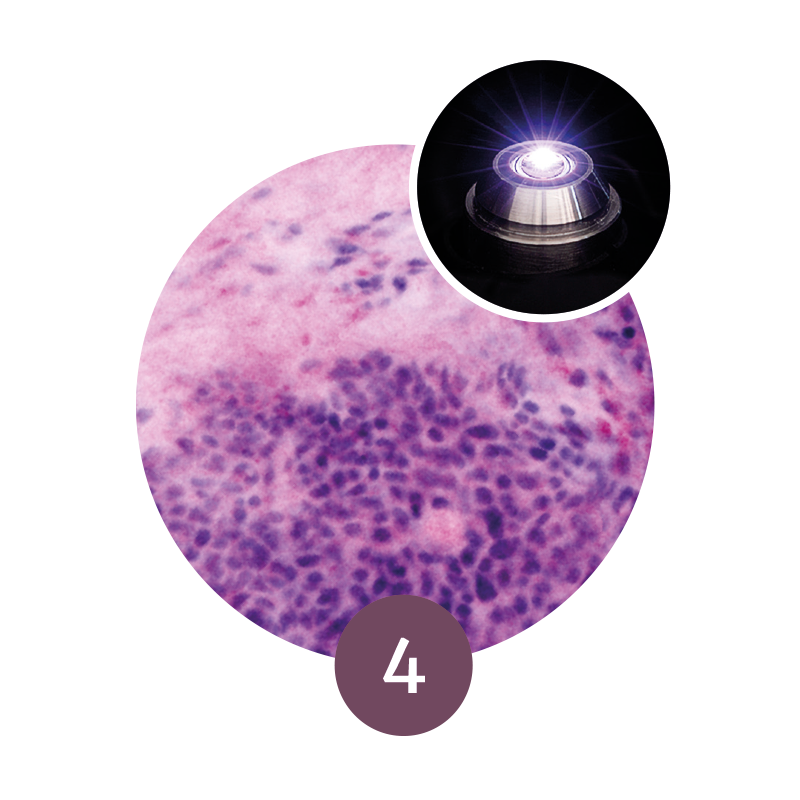

Step 4: Confocal Imaging

The VivaScope 2500 rapidly scans the excised tissue and reveals the cellular

morphology.

Image courtesy of Dr Javiera Pérez-Anker.